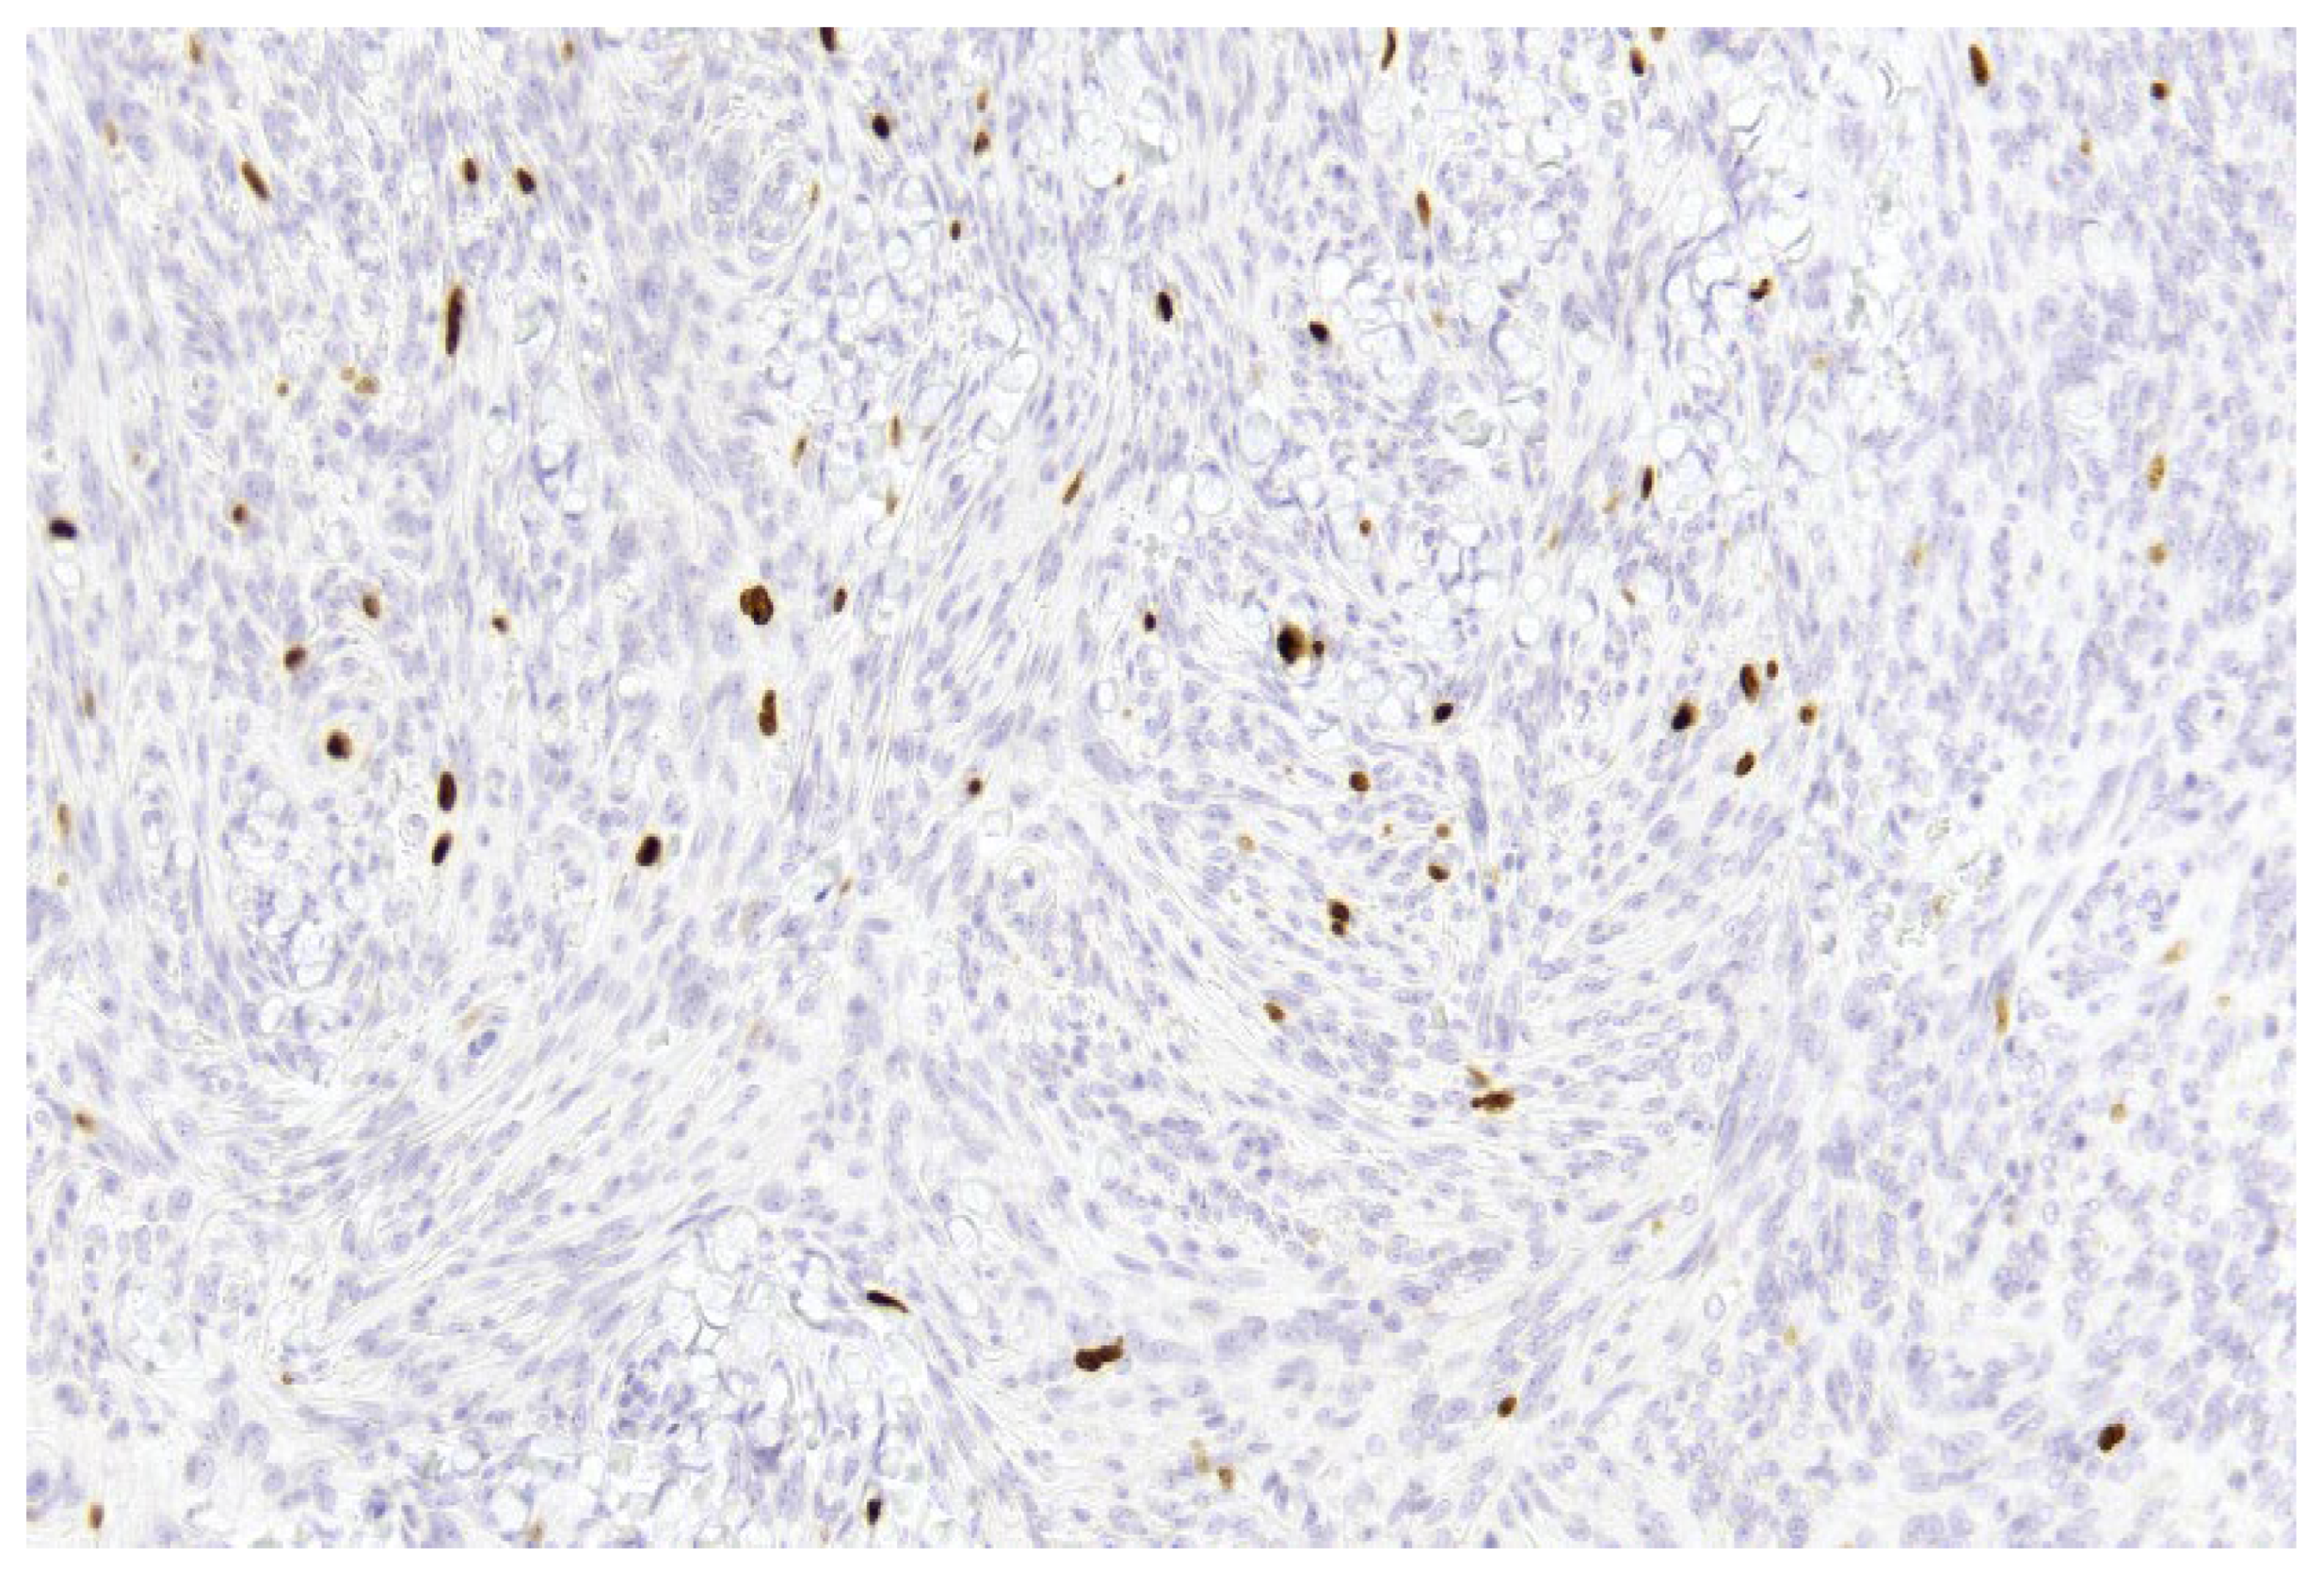

- Improved discrimination of neoplastic versus non-neoplastic cells: Unlike single-slice Ki-67 immunostaining (Figure 1), dIHC detects both markers on the same section, allowing precise differentiation between proliferating meningothelial tumour cells and components of the non-neoplastic microenvironment. EMA highlights the cytoplasm of meningothelial cells in brown, while Ki-67 marks proliferating nuclei in red. Only double-positive (EMA+/Ki-67+) cells are included in the PI count (Figure 2), whereas Ki-67-positive but EMA-negative elements (e.g., macrophages, lymphocytes, endothelial cells) are excluded (Figure 3).

Figure 1. Example of a single-slice Ki-67 staining in a grade 1 meningioma (case 1). Brown-stained nuclei indicate cells in the proliferative phase (10× magnification).